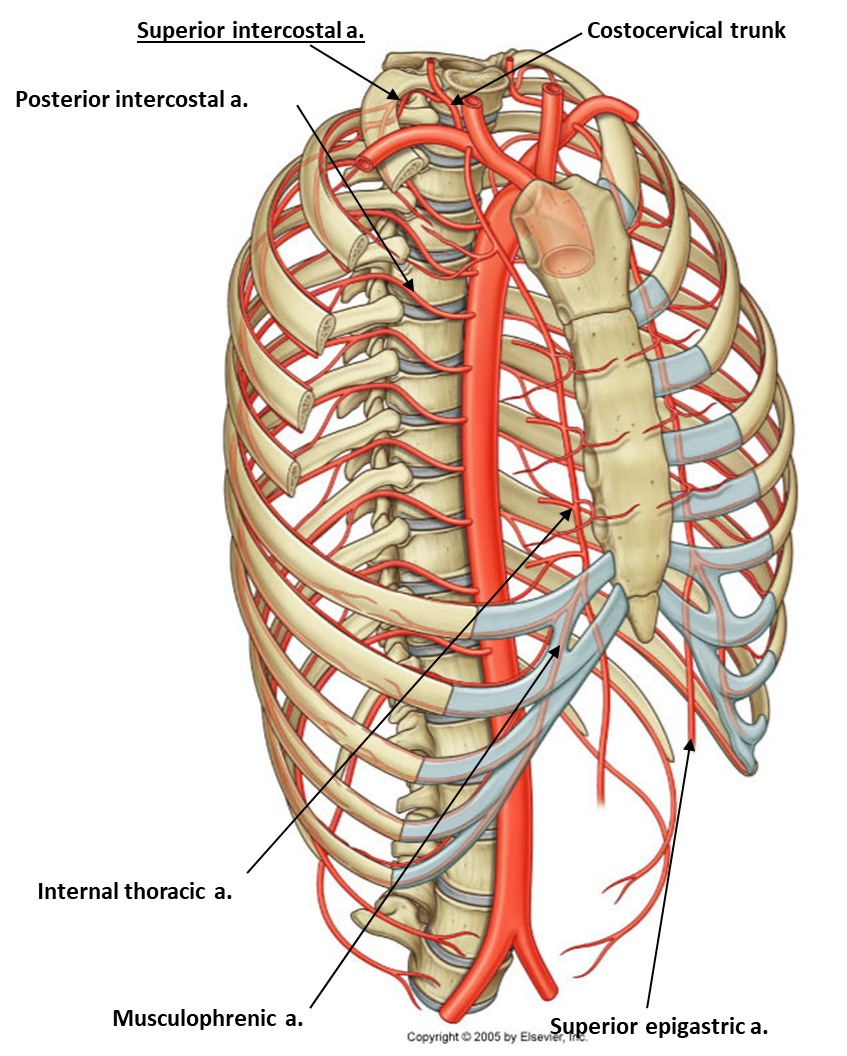

arterial supply

Posterior intercostal arteries

Mostly originate from the thoracic aorta

Anterior intercostal arteries

Originate from internal thoracic arteries for the upper spaces and;

Musculophrenic arteries for the lower spaces.